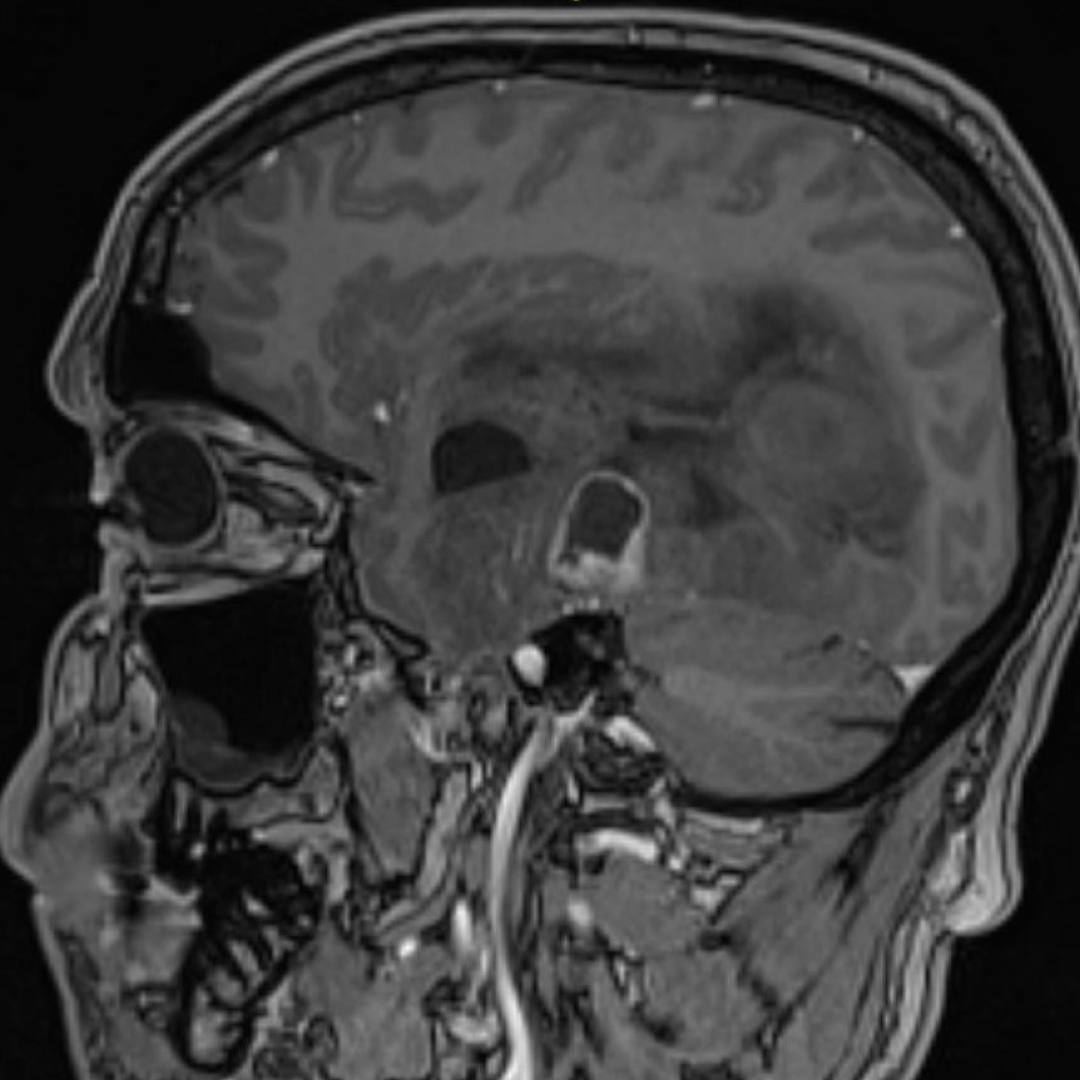

При проведении МРТ головного мозга выявлена опухоль правой височно-теменной области с переходом на островок, вовлечением базальных ядер справа и мозолистого тела с выраженным перифокальным отеком с дислокацией срединных структур мозга влево, компрессией правых бокового и третьего желудочков, среднего мозга.

При введении контрастного препарата визуализировался участок интенсивного кольцевидного накопления по периферии кистозного компонента опухоли.